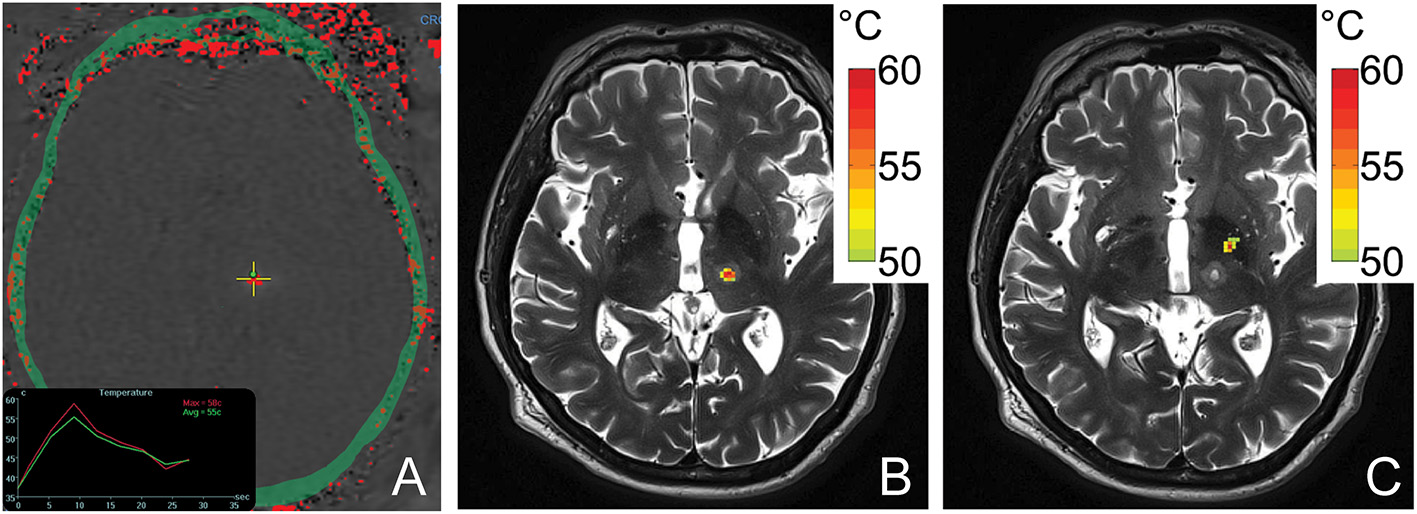

Simulated temperature maps for both VIM (Figure 4B) and GPi (Figure 4C) ablation on a single ET patient with the same sonication duration and power were rendered. The estimated peak temperature was 59.8 °C and 57.8 °C at the VIM and GPi targets, respectively. On the VIM target, the simulated peak temperature was quite close to the peak temperature (59.8 °C) recorded by MR thermometry (Figure 4A) during the treatment under the same conditions.

Figure 4

An MR thermometry image acquired during the treatment of ET with focused ultrasound thalamotomy showing 58°C was achieved as the maximum temperature on this patient (A). An example of temperature simulation results is shown when targeting VIM (B) and GPi (C) on the same patient. The temperature fields were registered to the post 1-day T2-weighted images. The globus pallidus internus lies antero-lateral compared to the ventral intermediate nucleus.

An acoustic and temperature field simulation demonstrated a higher peak temperature for thalamotomy than pallidotomy in the same ET patient, an internal control. The close estimated peak temperature by simulation compared with the treatment data indicated the accuracy of the simulation model. The simulated thermal profiles also closely resemble those observed in ET and PD treatment cases (22, 23). GPi lesions assume an elongated, ellipsoid shape extending in the inferolateral to superomedial direction due to the off-center target location which results a larger mean incident angle and therefore, an uneven energy distribution (22). These same factors result in an overall reduced peak acoustic intensity generated at the GPi compared to VIM, with resulting lower achievable peak ablation temperatures. In contradistinction, the near-center location of the VIM results in spherical lesions as well as, on average, a higher peak temperature under the same sonication conditions.